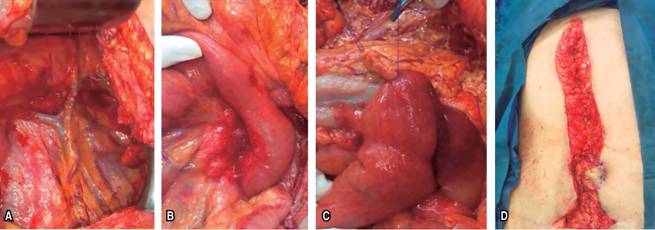

Se proporcionó tratamiento conservador durante tres semanas sin mejoría, por lo que se ingresa a la paciente al servicio de urgencias donde es tratada inicialmente con descompresión nasogástrica e hidratación intravenosa sin remisión de la sintomatología. Se decide procedimiento quirúrgico de urgencia, se efectuó duodenoyeyunostomía abierta, en la cual se liberó el ligamento de Treitz y se realizó una anastomosis de la tercera porción de duodeno hacia yeyuno a 10 cm distal de la unión duodeno yeyunal (Figura 3). El periodo postoperatorio transcurrió sin incidentes y la paciente comenzó una dieta blanda el día dos. La paciente fue dada de alta al quinto día, con seguimiento en una clínica ambulatoria sin complicaciones.

El paciente puede presentar síntomas agudos de obstrucción intestinal, como en nuestro caso, y síntomas crónicos como dolor abdominal recurrente, saciedad precoz y plenitud postprandial.2 La dilatación gástrica aguda puede dar lugar a varias complicaciones como la deshidratación, la alcalosis metabólica, la necrosis gástrica y la insuficiencia circulatoria sistémica.7 El diagnóstico definitivo se establece mediante tomografía, resonancia magnética o angiografía.3 Los casos no complicados de síndrome de AMS generalmente se manejan de forma conservadora en primera instancia con el objeto de tratar los síntomas de la obstrucción intestinal con descompresión gástrica mediante la inserción de sonda nasogástrica, rehidratación y reemplazo de electrolitos, así como el manejo nutricional y la restauración del peso apropiado para conservar el ángulo normal entre las dos arterias involucradas para evitar la recurrencia.1 Cuando falla el tratamiento conservador, se indica el manejo quirúrgico. Se dispone de varias opciones quirúrgicas como la división del ligamento de Treitz (procedimiento de Strong), duodenoyeyunostomía y gastroyeyunostomía.3 La duodenoyeyunostomía es el procedimiento que más se utiliza con una tasa de éxito mayor de 90%.1 En nuestro caso, optamos por una duodenoyeyunostomía abierta después de optimizar el estado general de la paciente debido a la evolución de los síntomas.